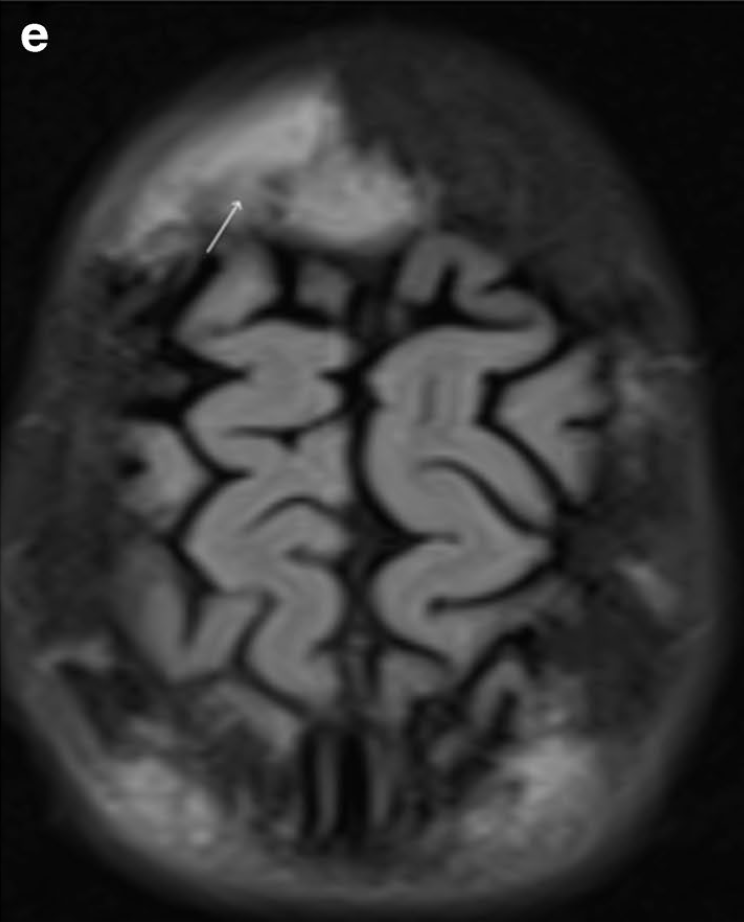

Hématomes sous-périostéaux bilatéraux

Les infarctus osseux peuvent parfois impliquer l'orbite lors d'une crise vaso-occlusive

=> hématomes sous-périostéaux

Diagnostic: CT C+ exclut infection

TRT: décompression chirurgicale